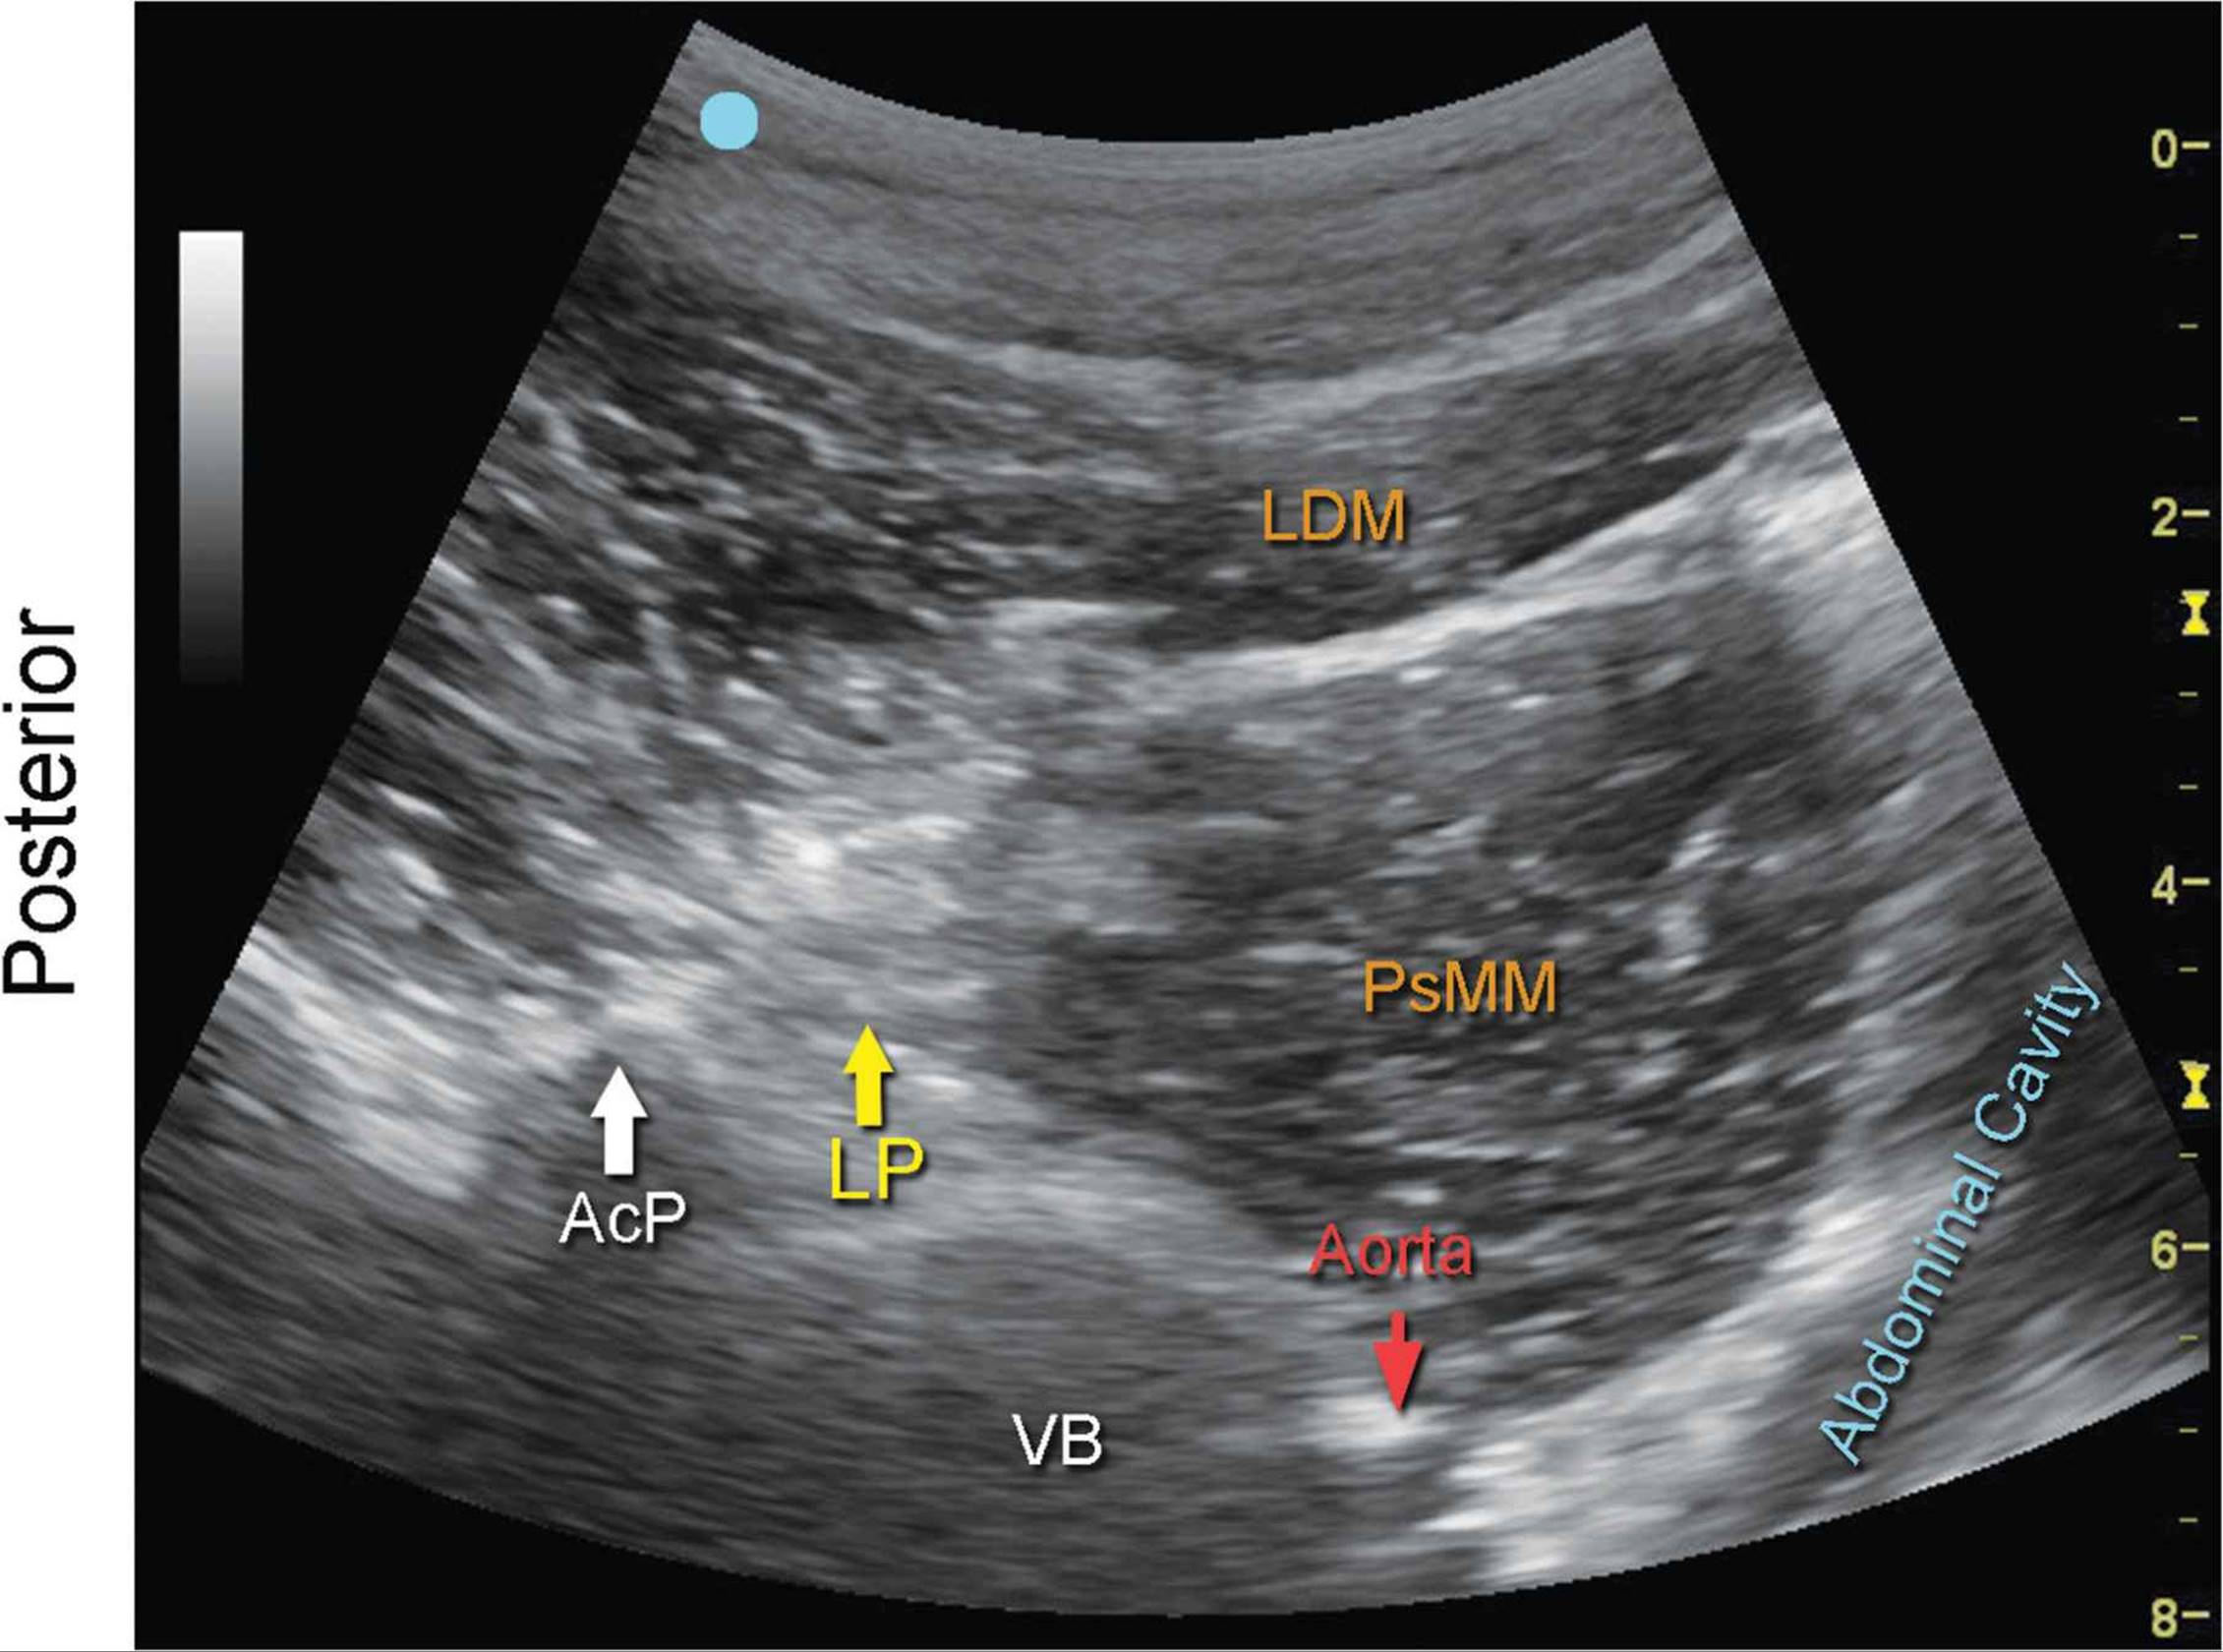

Lumbar Plexus, Transverse View

FIGURE 7.40.1A Ultrasound transducer position to image the lumbar plexus, transverse view.

FIGURE 7.40.1B Ultrasound image of the lumbar plexus, transverse view.

7.40.1C Labeled ultrasound image of the lumbar plexus, transverse view.

FIGURE 7.40.1D Labeled cross-sectional anatomy of the lumbar plexus, transverse view.

Abbreviations: SP, Spinous process; Map, Mammillary Process; ESM, Erector Spinae Muscle; QLM, Quadratus Lumborum Muscle; LP, Lumbar Plexus; PsMM, Psoas Major Muscle; VB, Vertebral Body; MfM, Multifidus Muscle; LDM, Longissimus Dorsi Muscle.